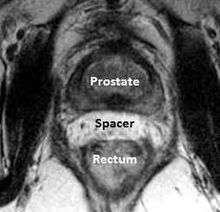

A new method to reduce rectal radiation injury in prostate cancer patients involves the use of an absorbable spacer placed between the prostate and rectum.

Such spacers are commercially available in some regions, and are undergoing clinical trials in others.[21] By temporarily altering the anatomy these products have the potential to allow for improved cancer targeting while minimizing risk to neighboring healthy tissues. Prostate Rectum Spacers should be compatible with all prostate cancer radiotherapy treatments including 3D conformal, IMRT and stereotactic radiation and brachytherapy.